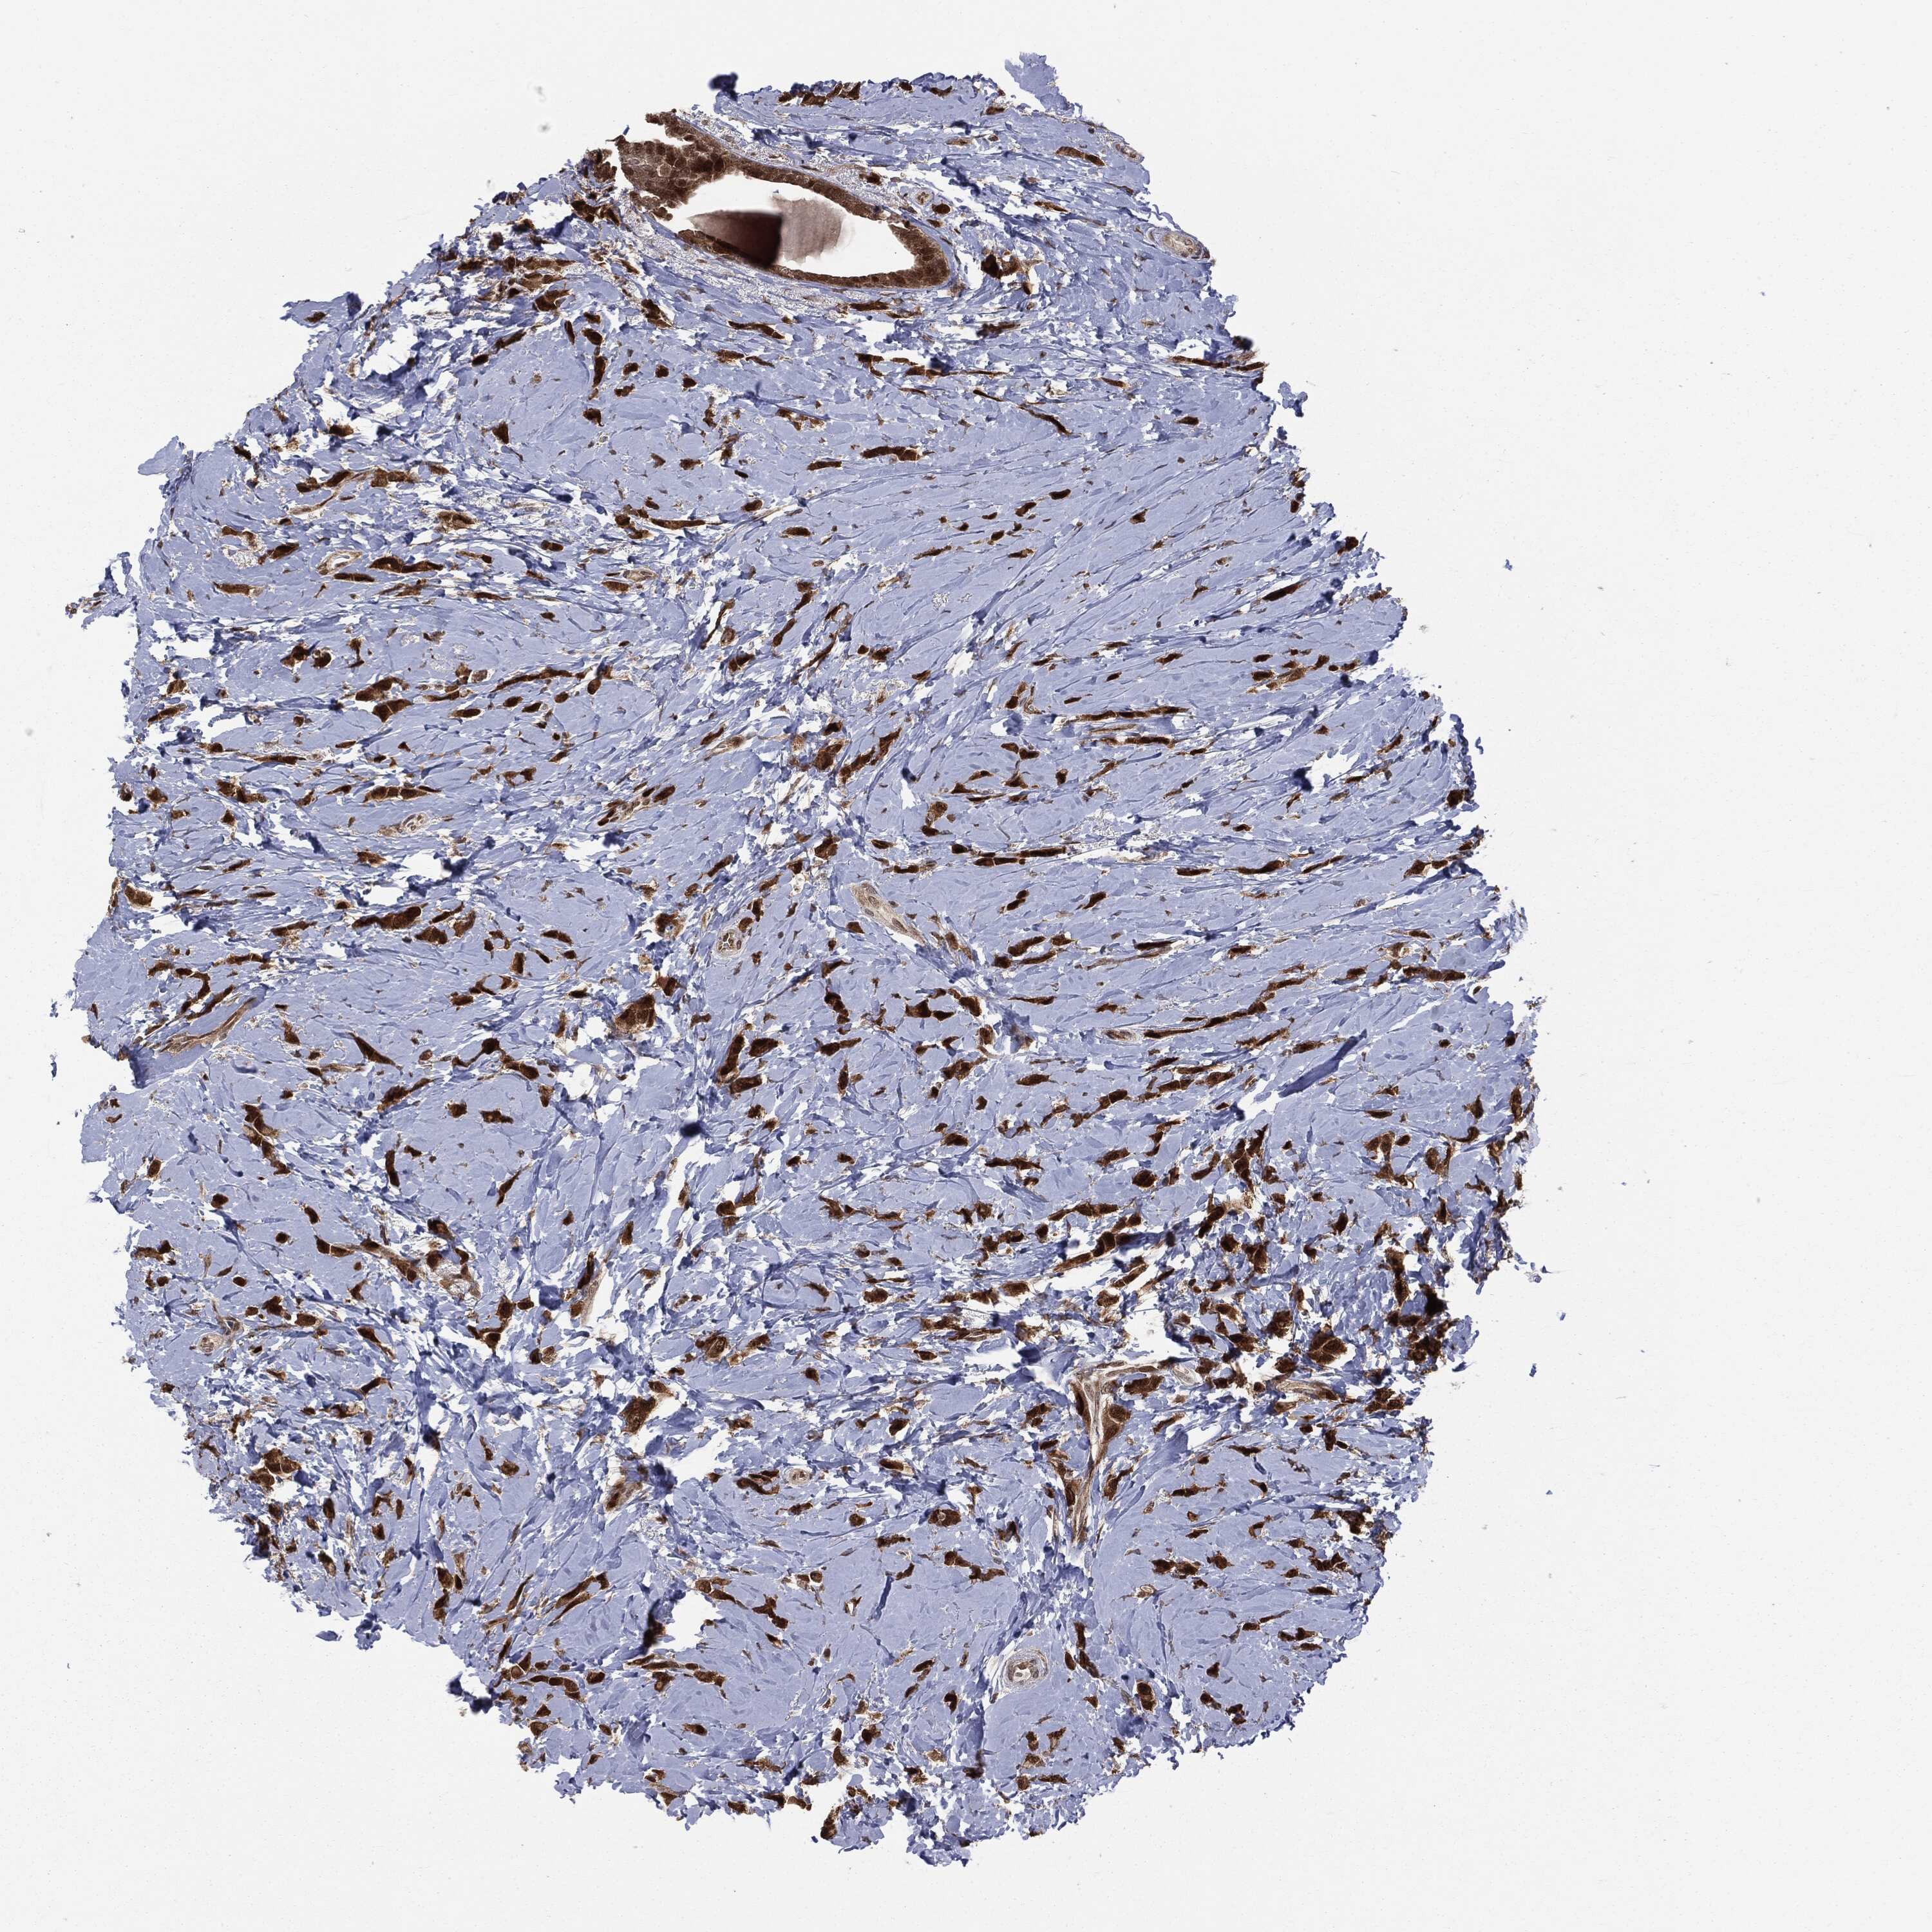

BRCA TCGA BRCA VALIDATION PROTEIN EXPRESSION

ANTIBODIES

AND

VALIDATION